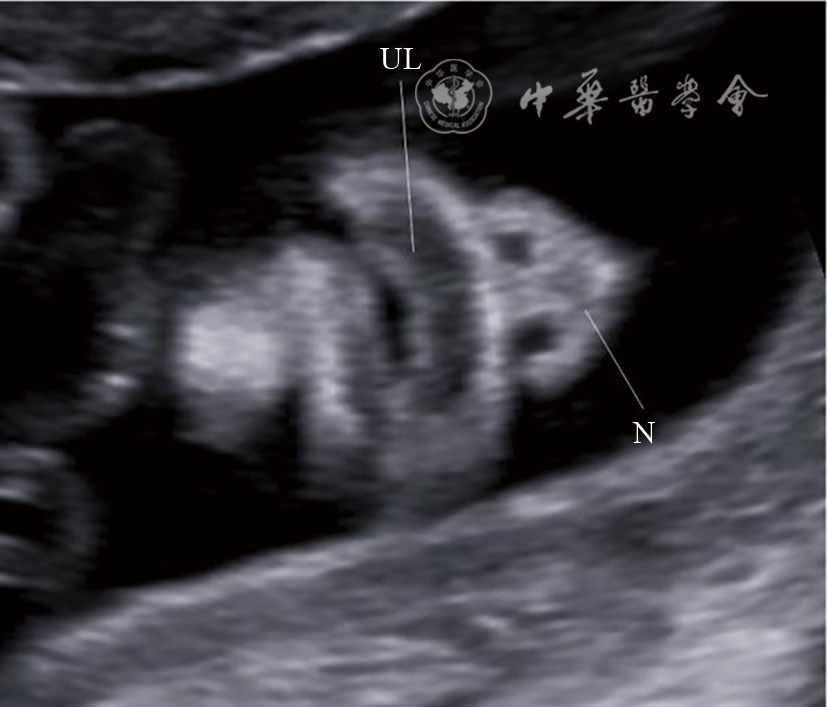

图14 颜面部正中矢状切面超声图像 注:NB为鼻骨;NA为鼻尖;UL为上唇;LL为下唇;ME为下颌